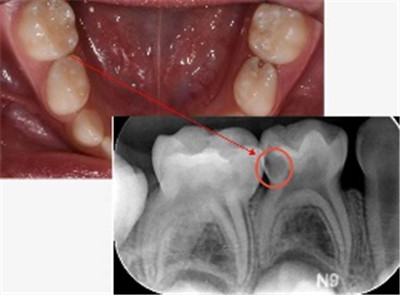

2.位置的欺骗性:

很多龋病发生在牙齿的邻面(牙缝之间)或者后牙的窝沟深处,这些地方肉眼很难直接看到。只有当洞扩大到一定程度,您用舌头才能舔到,或者食物开始塞牙时,您才会“突然”发现它。